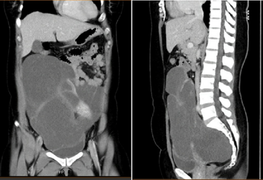

Khối u trong bụng chị A. chiếm hết 2/3 ổ bụng, chèn ép ruột, bọng đái lại dính vào ruột non, ruột già, tử cung, buồng trứng, vách chậu... khiến bác sĩ không khỏi đau đầu khi phẫu thuật.